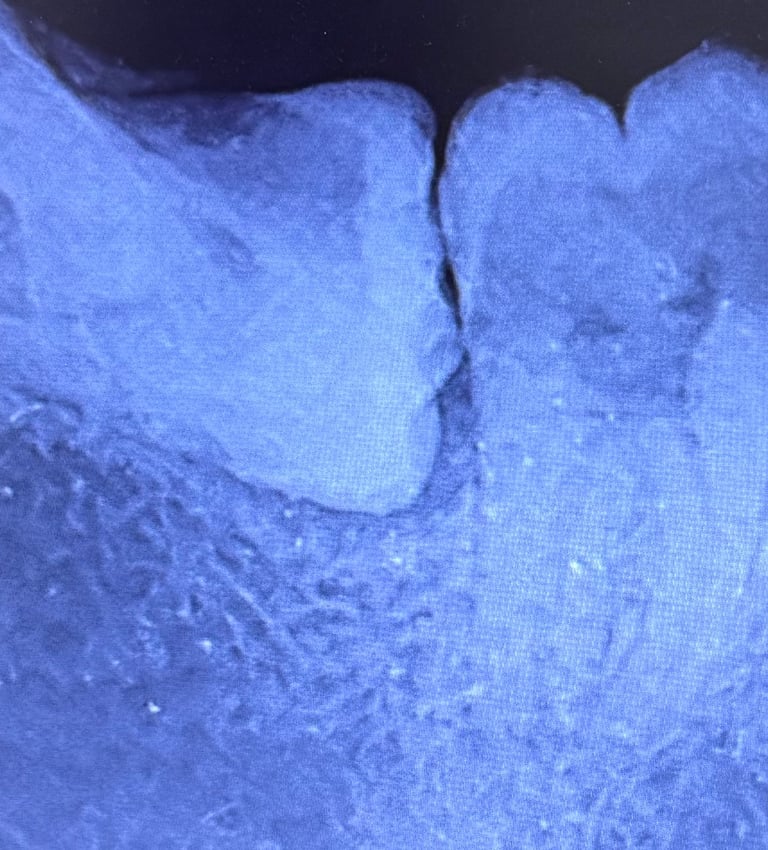

Prima...

...e dopo il trattamento